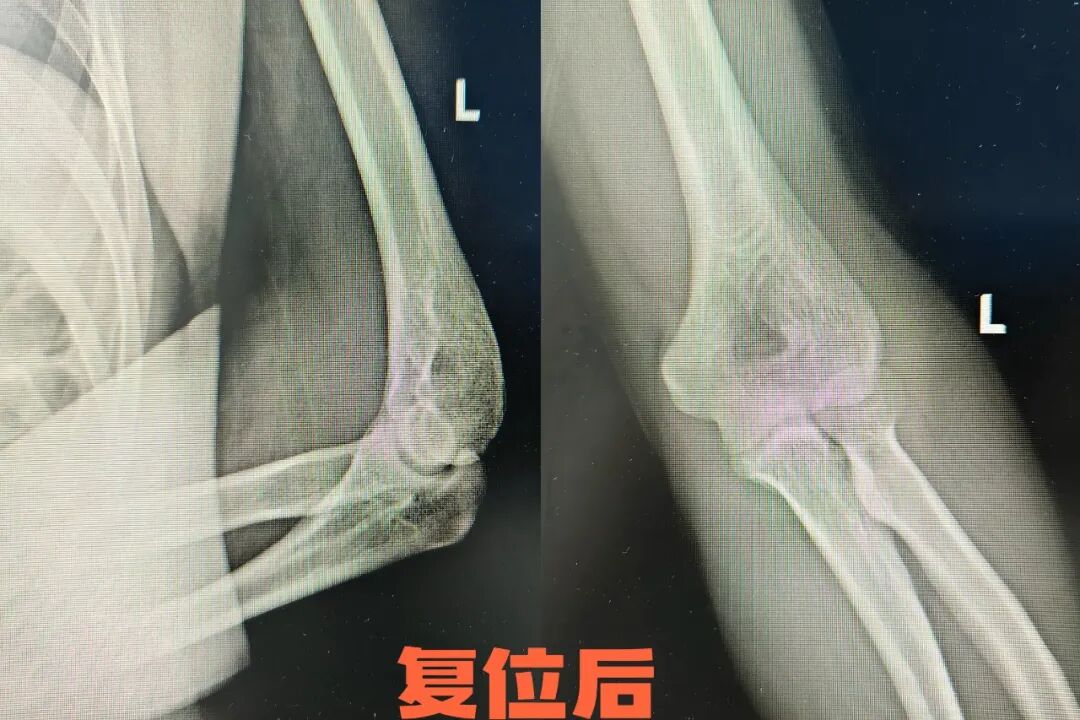

病例二

25岁的小张在篮球比赛中与队友碰撞后倒地,左肘呈屈曲位畸形,肿胀严重。小张立即来到长治二院急诊科治疗,急诊科团队迅速评估伤情,经X片检查确认患者为肘关节后脱位,立即实施牵引复位法。创伤骨科一病区杨志军医生与急诊科何龙医生双手分别握住患者上臂和前臂,进行手法牵引复位。复位后疼痛显著减轻,小张肘关节活动度恢复。随后用支具固定4周,配合康复锻炼,重返球场不是梦。